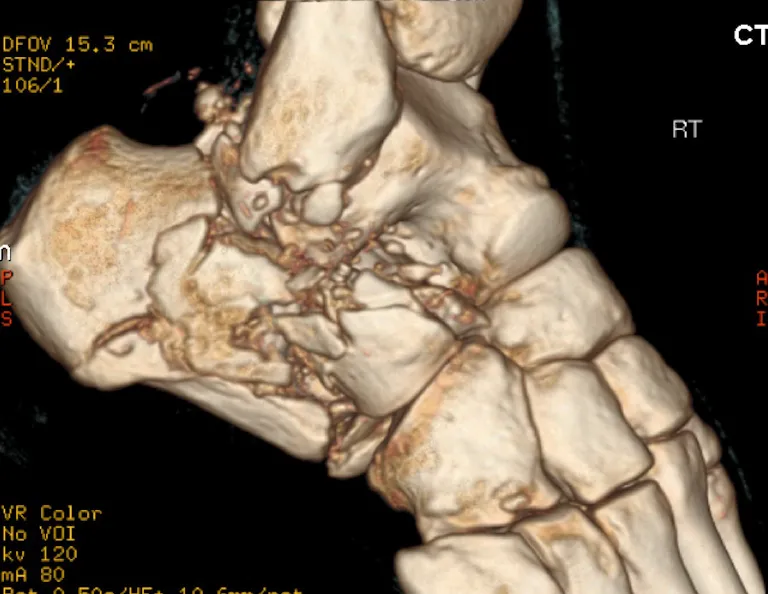

A CT scan is essential to accurately evaluate:

- The degree of articular involvement

- The number of fracture fragments

- Joint displacement

- Overall fracture morphology

The CT will identify the severity of the injury and whether surgery is indicated or not.

Severity is determined on the CT by:

- The degree of joint displacement

- Sanders classification on CT

Number of fragments and increasingly displaced. Greater disruption to the subtalar joint. Disruption of the calcaneocuboid joint.